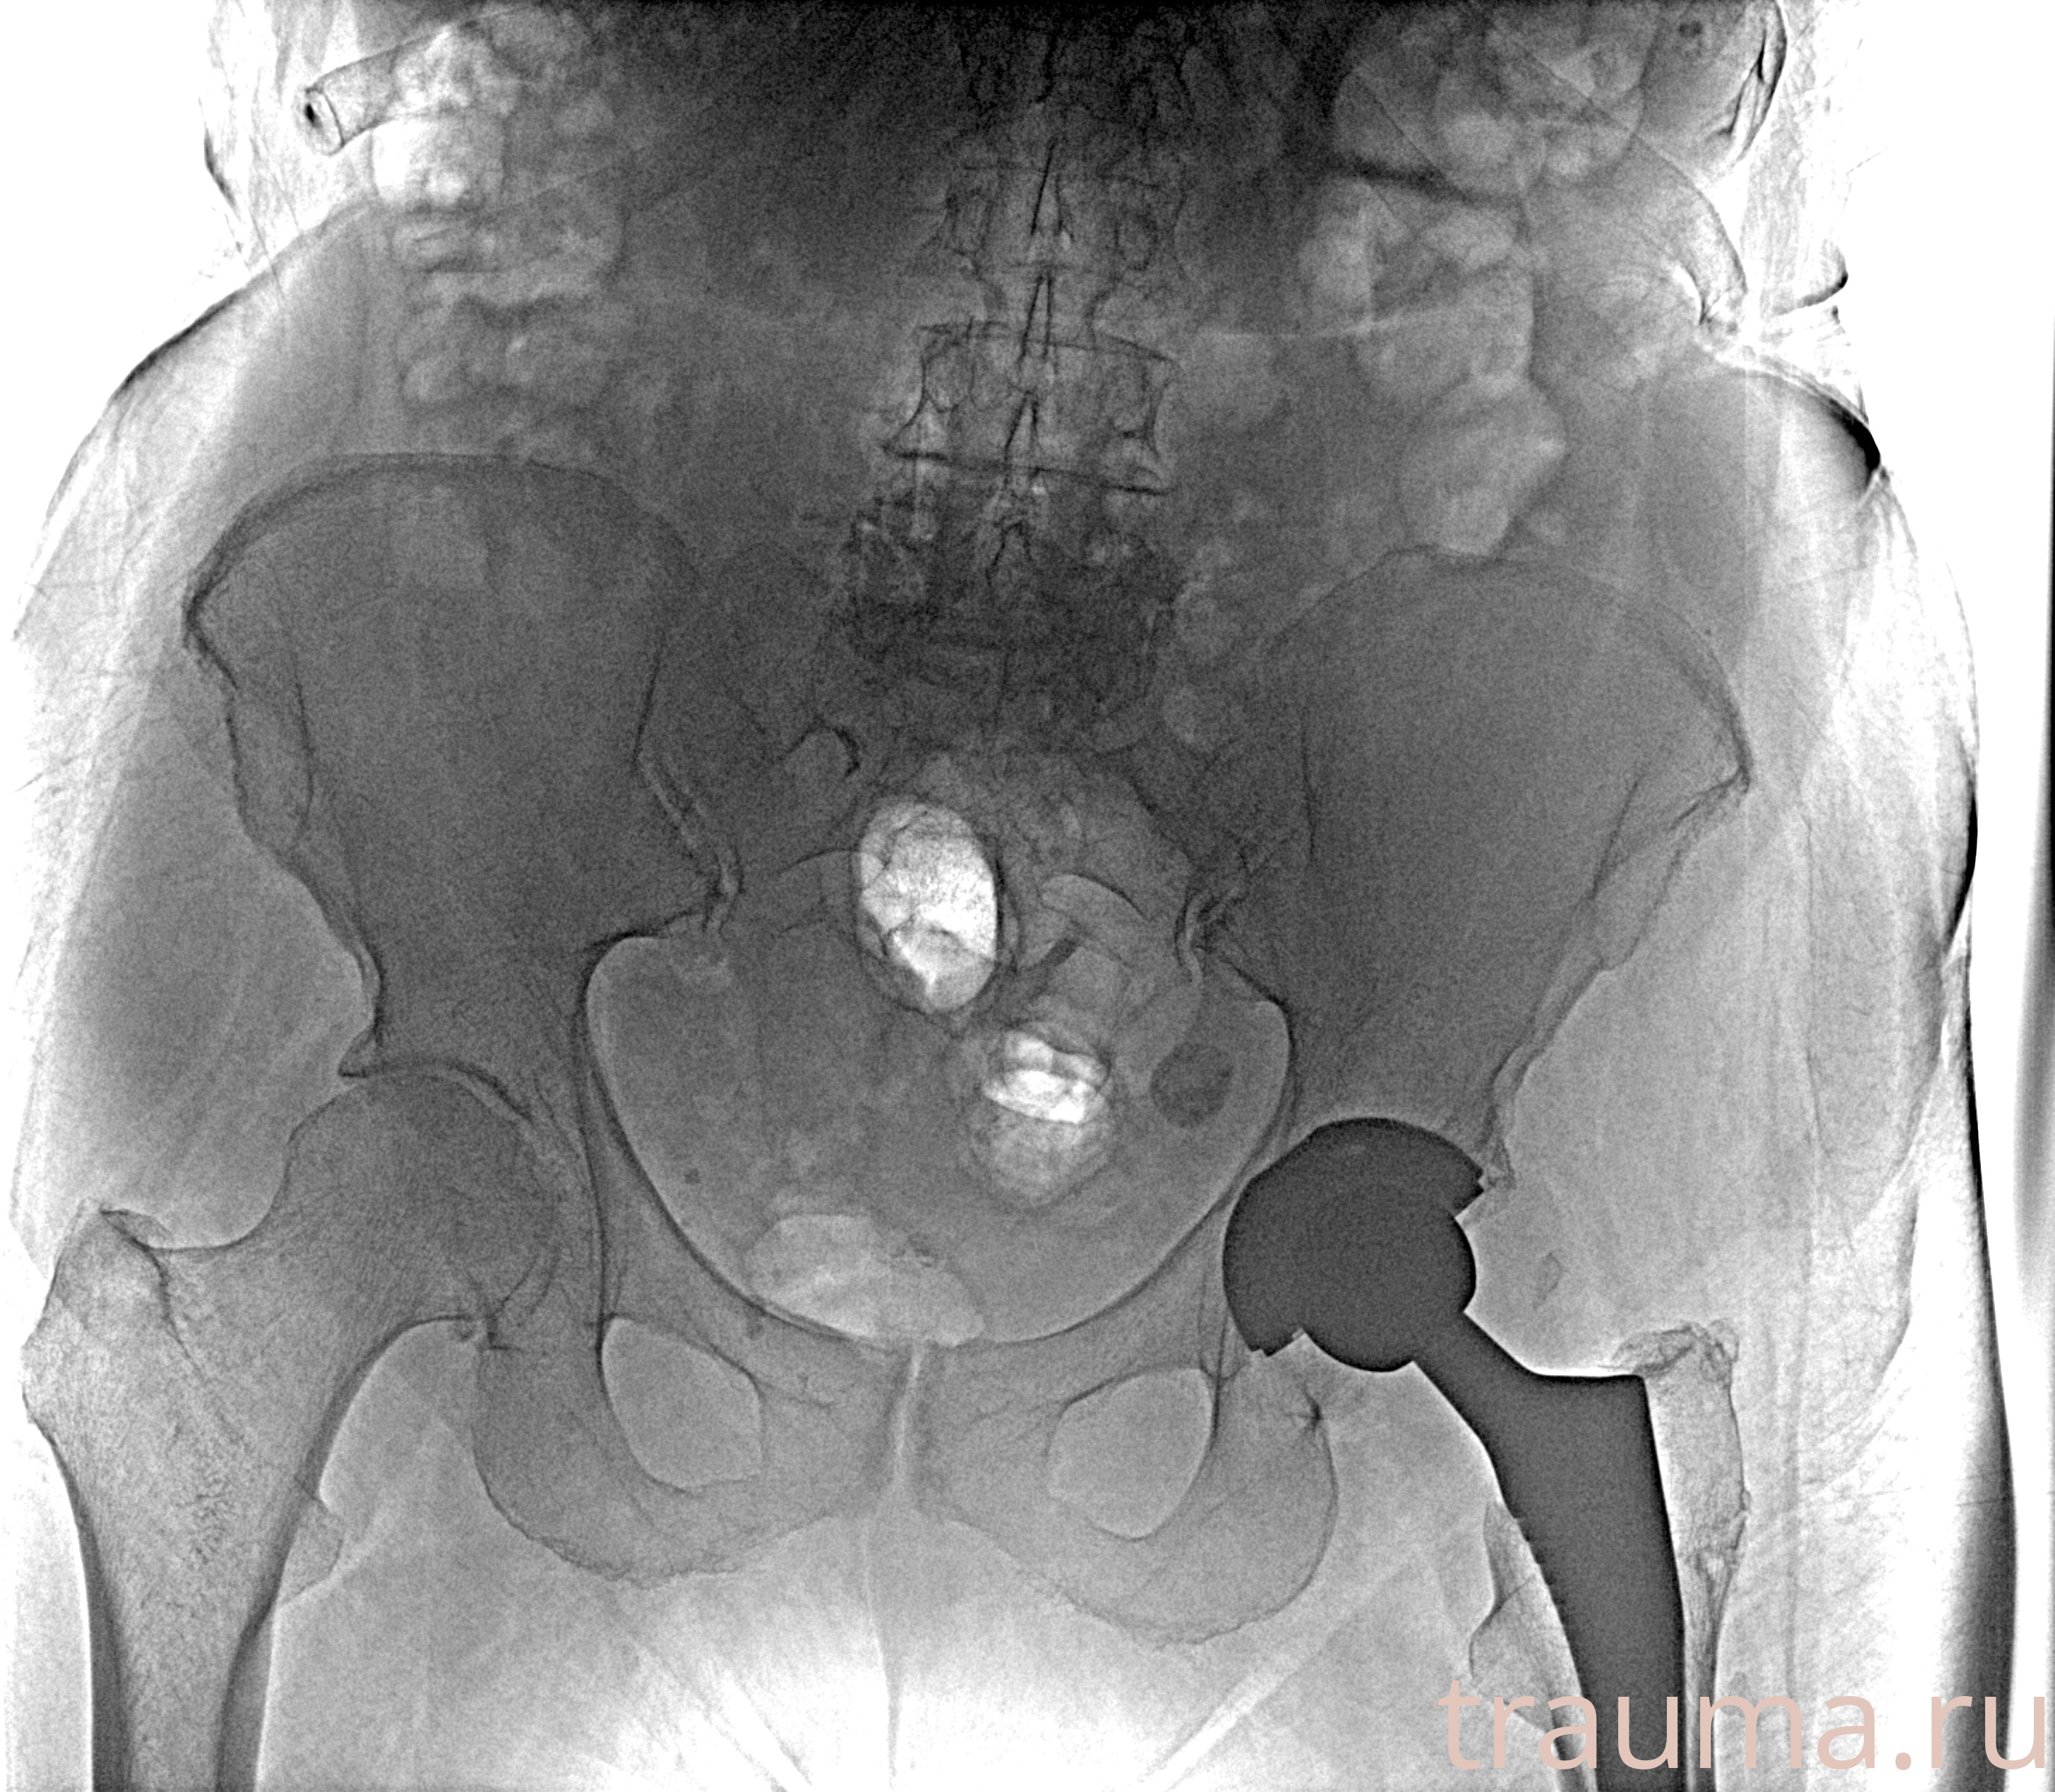

Рентгенограммы

Рентген на дому: по вашему адресу приезжает врач-рентгенолог, травматолог-ортопед с мобильным рентгеновским аппаратом, проводит диагностику травмы или заболевания, делает необходимые рентгенограммы, дает рекомендации по дальнейшему лечению. Получить качественные снимки в домашних условиях возможно благодаря уникальной методике, разработанной МосРентген Центром для института  Склифосовского